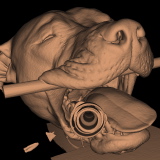

Ausdruck der Bilddaten als plastisches Modell

Der Ausdruck der CT-Bilddaten als plastisches Modell ist ebenfalls möglich.